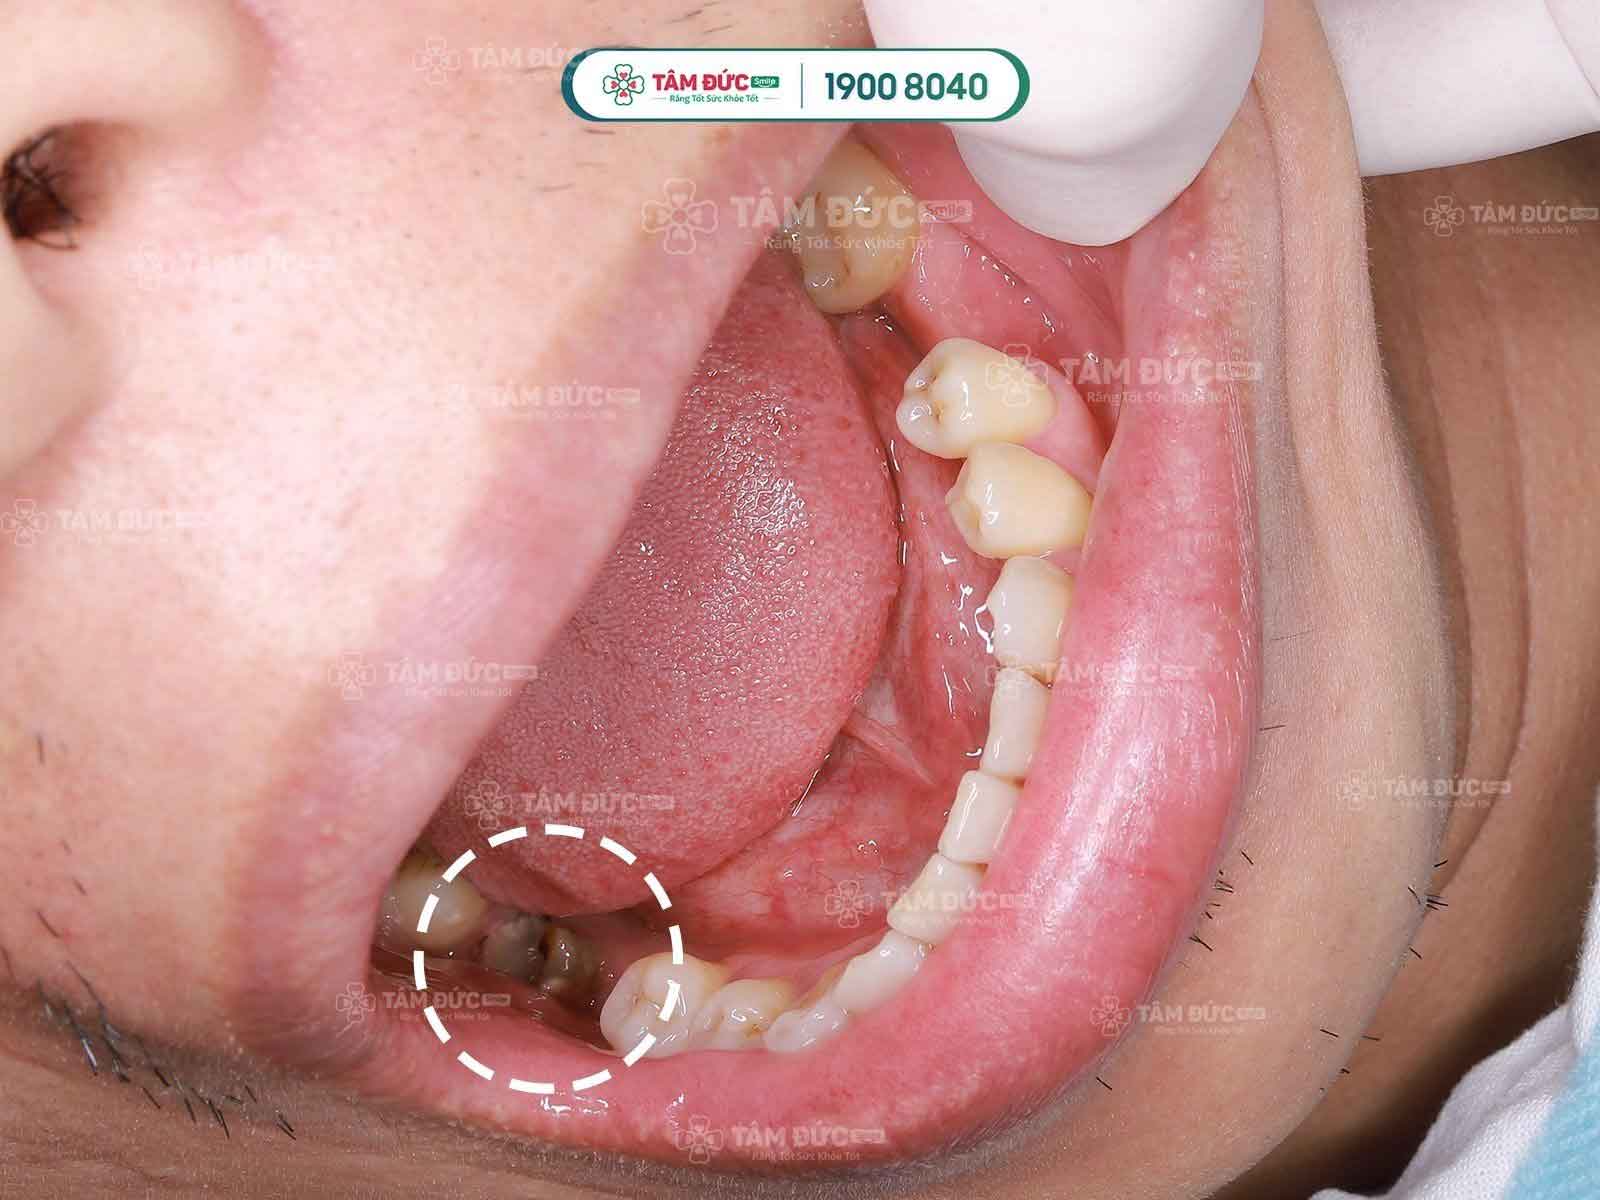

Răng hàm bị sâu chỉ còn chân răng thường gây viêm nhiễm

Trường hợp sâu răng nặng: gây viêm tủy, phá hủy mô răng nặng, khi đó tùy vào mức độ viêm nhiễm, bác sĩ sẽ tiến hành điều trị nội nha và trám phục hồi hình dáng răng. Trường hợp xấu nhất, khi các phương pháp điều trị không hiệu quả, sâu răng ăn gần hết răng, hoại tử tủy, viêm nhiễm nặng và có nguy cơ ảnh hưởng tới các răng bên cạnh, khi đó, bác sĩ sẽ chỉ định nhổ bỏ.